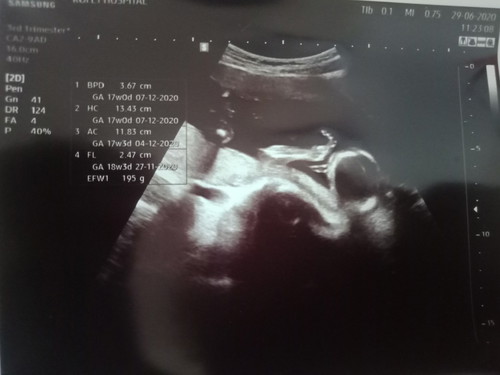

ท้องได้ 18 W แล้ว หมอบอกว่าน่าจะเปนผู้ชาย 70% ไครู้ว่าชายจิงไหม บอกหน่อย ดูตรงไหน?

ตรวจตอน18w. เหมือนกันค่ะหมอบอกชาย80%แต่จะให้ชัวก็ต้อง20w.ขึ้นไปตอนนี้24w.ชาย100%เลยค่ะ😂